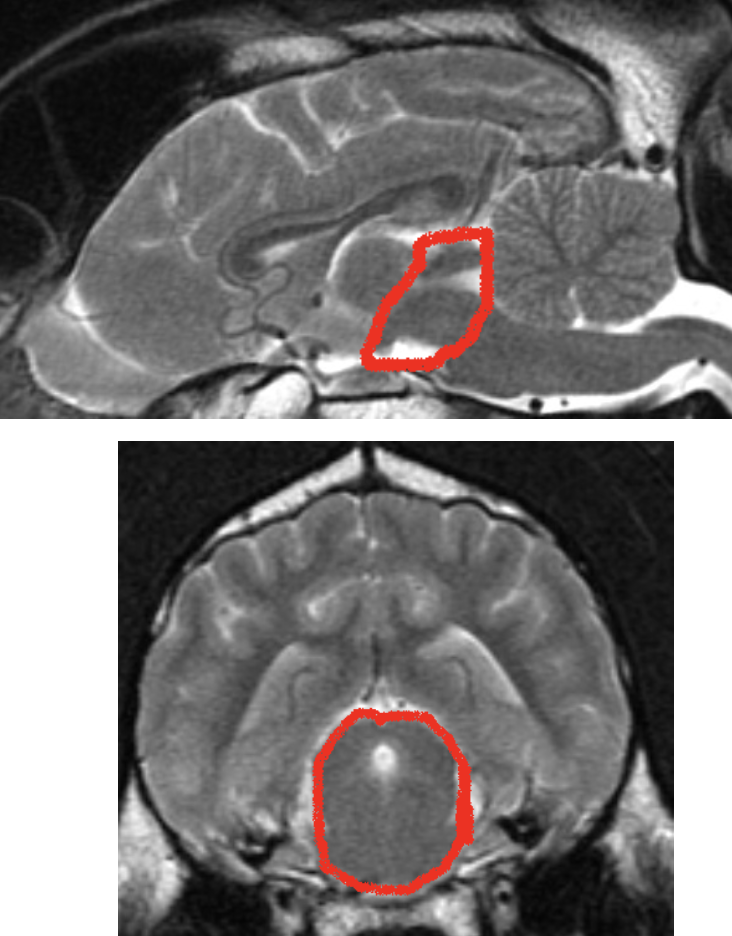

what structures are shown

mesencephalon